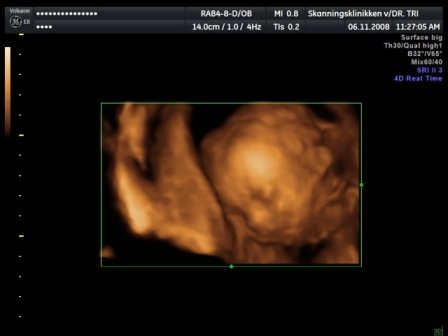

kaptunk félórás dvd-t a vizsgálatról, kétoldalas leírást a bébiről, 3 fekete-fehér képet és egy színeset kinyomtatva, és 23-at egy másik dvd-n:D tök rendes volt a csaj... de a kis drágám nagyon dugdossa az arcocskáját.. mindent megmutat, de az arca az magánügy úgy gondolja :D azért elég makacsak voltunk úgyhogy nagy nehezen sikerált egy profil :D azt mondta a dokinő hogy nagyon nagyon aktív bébi :D és teljes bizonysággal kistökös :D:D:D Kép bébi 4D Kép a kis tökös Kép kezek-lábak